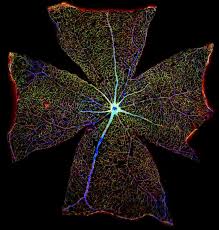

Những bức ảnh về khoa học nhưng không kém phần nghệ thuật của Giải thưởng Wellcome Image

Bề mặt võng mạc của chuột. |